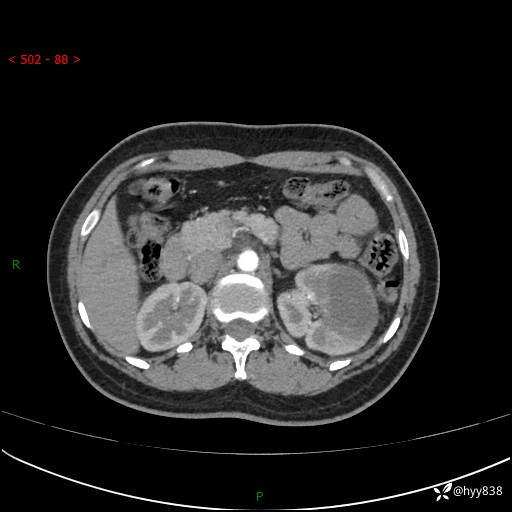

现病史:患者于1周前因左侧腰腹部间断胀痛不适,无恶心呕吐,无明显肉眼血尿,无畏寒发热,无尿频尿急,起病初,患者来我院就诊,查CT提示左肾低密度影,外周血提示:白细胞11.25*10^9/L.行抗感染治疗后未见明显好转,06-18泌尿系增强CT提示左肾类圆形低密度占位(脓肿?肿瘤?),大小:4.0*3.2cm,为求进一步治疗,门诊以“左肾占位”收住我科。 起病以来,患者精神佳,饮食、睡眠良好,大小便正常,体力体重无明显变化。

双肾CT平扫+增强